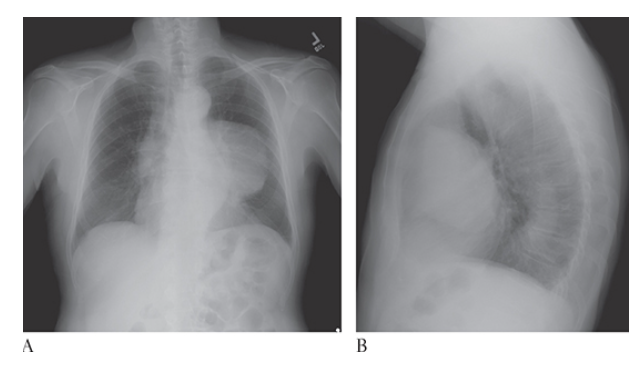

What is A

Superior Vena Cava Syndrome. CECT coronal and MPR CECT sagittal

What is B

Superior Vena Cava Syndrome. CECT coronal images show significant narrowing of the superior vena cava with development of multiple collaterals.

Superior Vena Cava Syndrome. Axial CECT shows significant narrowing of the superior vena cava with development of multiple collaterals.